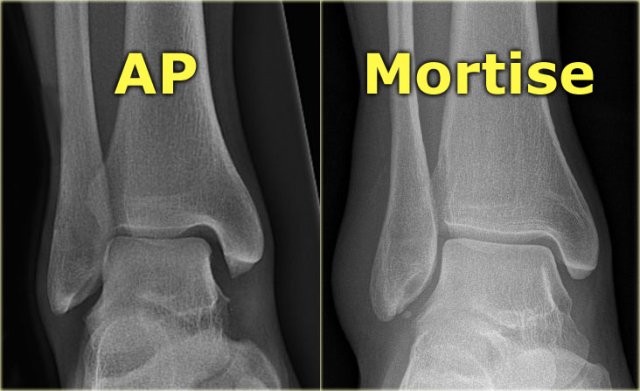

A basic radiographic examination of the injured ankle consists of an AP-view, a Mortise-view and a lateral view.

The Mortise-view is an AP-view taken with a 15-25? endorotation of the foot.

The technologist turns the foot inwards until the lateral malleolus is at the same height as the medial malleolus.

This view visualizes both the lateral and medial joint spaces.

On a true AP-view the talus overlaps a portion of the lateral malleolus, obscuring the lateral aspect of the ankle joint.